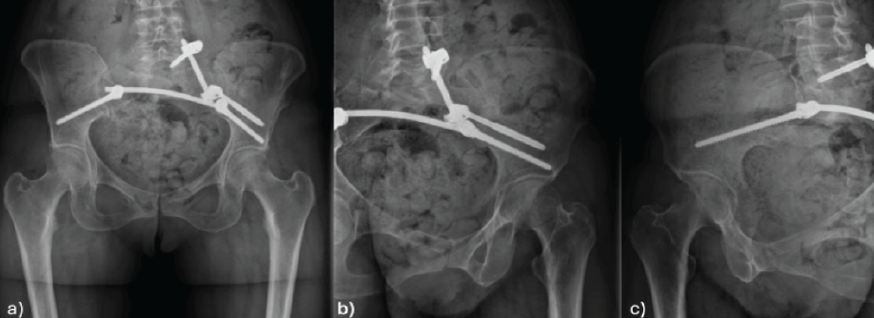

The fracture was managed with percutaneous posterior lumbopelvic fixation. Robust stabilization was achieved by employing unilateral pedicle screw instrumentation from L5 to the iliac bone, reinforced with interiliac fixation (Fig. 5). The procedure was performed without complications.

Figure 5: Post-operative pelvic X-rays: Anteroposterior (a), left sacral ala (b), and right sacral ala (c) view.

Five-years post-operatively, the patient maintains an adequate clinical follow-up without pain or functional deterioration. Imaging follow-up indicates stability of the lumbopelvic osteosynthesis, without relevant structural complications. SPECT-CT shows no signs of tumor recurrence (Fig. 6).